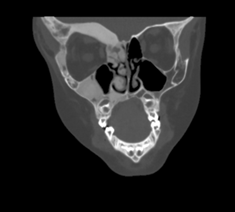

-expansion of involved bone -multilocular HONEYCOMB OR SOAPBUBBLE radiolucency posterior maxilla and mandible -age<30 women>men